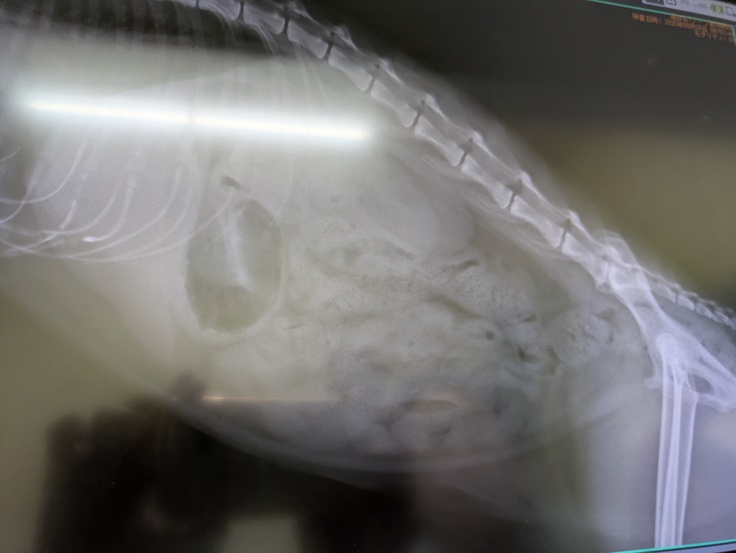

そして本日は[ちゃいろちゃん]の受診日。

とても凶暴なので麻酔下で出来る限りの検査をすることになりました。

一番はウイルス検査。残念ながらエイズは陽性でした。

そして一般血液検査。

前回よりほとんど全ての数値が改善されていました。

ただ1点尿素窒素が高かったのですが腎臓に関わる他の数値は正常とのこと。

レントゲンも撮っていただき、若い猫の腎臓と変わらないとのことで問題なし。

膀胱、尿道も全て問題ないとのこと。

ただ、あまりに凶暴でまた検査という事態になっても大変なのでと腎臓に疾患があるか院外検査をお願いしました。

検査結果が分かりましたらまたお知らせいたします。

また尿単独の検査も少し濁りはあるものの問題なしとのこと。

安心いたしました。

多飲多尿は今までの過酷な外生活の名残ではないかとのこと。

水飲めるときは飲む。そういうふうになってしまったのかもしれないということです。